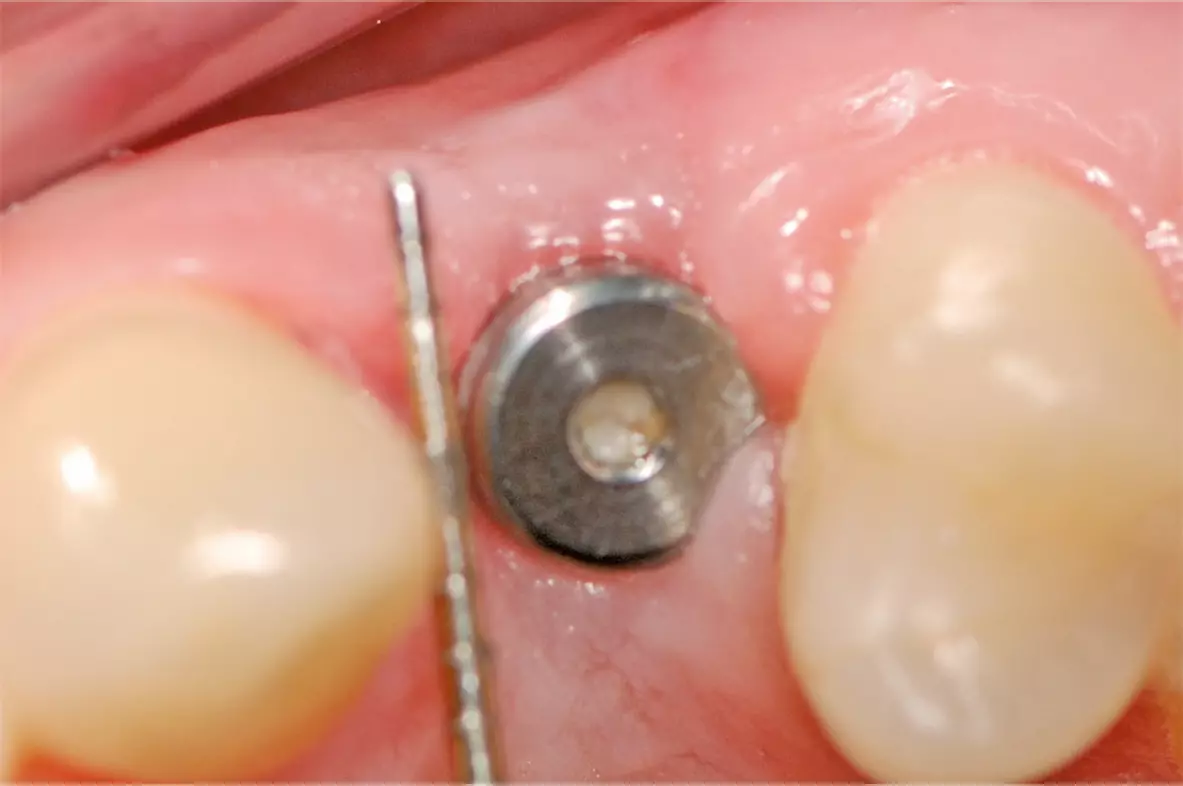

Nach ausführlicher Aufklärung und Beratung wurde die Extraktion des Zahnes 24 geplant. Zu diesem Zeitpunkt entschied sich der Patient gegen eine präventive Maßnahme zur Versorgung der Extraktionsalveole. Eine schonende Extraktion des Zahnes erfolgte komplikationslos unter gängiger Lokalanästhesie. Dabei konnte die vestibuläre Lamelle regelrecht erhalten werden (Abb. 2). Die Extraktionsalveole wurde mit einer Naht versorgt (Abb. 3). Ein Tag nach der Extraktion zeigt sich eine fibrinbelegte Wunde mit zeitgerechter und regelrechter Wundheilungsstatus (Abb. 4). Nach einer Woche wurde die Naht entfernt. Es zeigte sich zu diesem Zeitpunkt weiterhin eine fibrinbelegte Wunde mit einer okklusalen Mulde, die etwa 5 mm tief ist. Die Heilung war nach einer Woche also noch nicht komplett abgeschlossen (Abb. 5). In der frühen Wundheilungsphase berichtete der Patient beschwerdefrei gewesen zu sein. Drei Monate später stellte sich der Patient erneut vor mit dem Wunsch einen festsitzenden Zahnersatz zu bekommen. Die Extraktionsalveole zeigte eine vollständige Wundheilung und eine deutliche vestibuläre Knochenresorption (Abb. 6). Das Implantat konnte trotzdem eingesetzt werden und zeigt zum Zeitpunkt der Implantation eine adäquate Primärstabilität (Abb. 7). Nach drei Monaten wurde das Implantat freigelegt (Abb. 8) und anschließend mit einer Krone versorgt (Abb. 9).